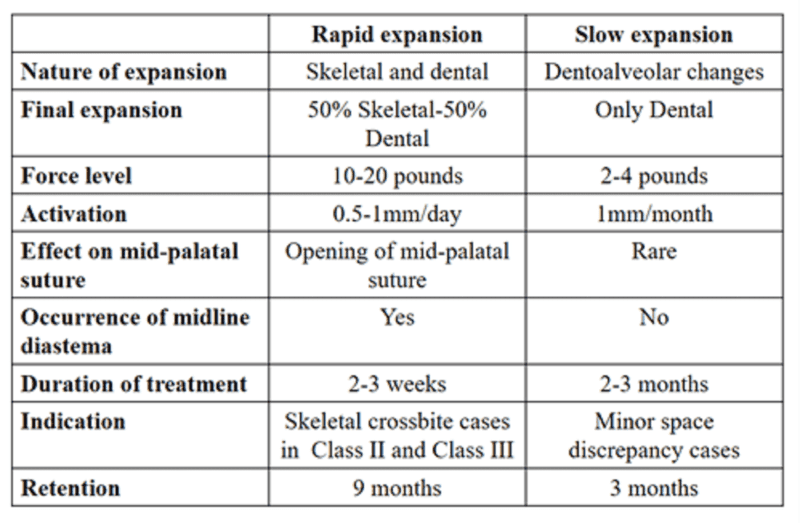

Comparison of effects of slow and rapid palatal expansion

- When the effects of both slow and rapid maxillary expansions are compared, there is no net difference in the skeletal and dental changes produced by rapid and slow maxillary expansions.

- According to various studies, after RME 10 mm of expansion is achieved of which skeletal expansion is 8 mm and dental expansion is 2 mm.

- After 4 months, 10 mm of the dental expansion is still present and only 5 mm of skeletal expansion is present. Hence, there is 5 mm of skeletal expansion and the remaining 5 mm account for dental movement.

- With slow maxillary expansion, after a 10-week period of expansion, the same amount of 5 mm of skeletal and dental expansion is produced.

- In rapid expansion, there is more skeletal relapse due to delay in the bone fill in the mid-palatal region after rapid expansion during which the relapse of the skeletal expansion occurs, whereas in slow maxillary expansion, the rate of expansion is close to the maximum rate of bone fill (physiological expansion).